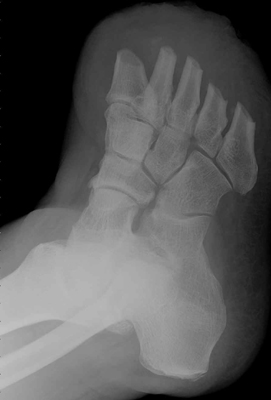

The images above demonstrate a transmetatarsal amputation through all five digits.

The bone edges are beveled and there is a generous soft tissue pad.